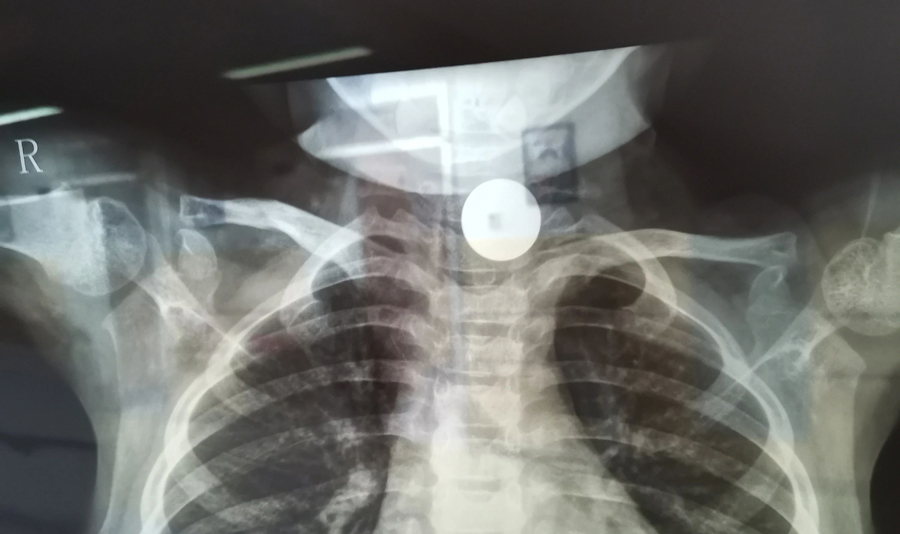

小花(化名)是4岁的小女孩,家住德惠市。小花曾说自己吞咽过一枚硬币并已排出,粗心的家长便没再关注。但此后一段时间里,小花出现进食缓慢情况且越来越重,家长这才怀疑硬币可能还在体内,所以带小花在当地医院拍了X光片,发现其食道入口处的确有异物。医生建议到上级医院手术,于是家长带孩子马不停蹄地赶到啪啪网 。

了解了患儿的情况后,国家儿童医学中心、首都医科大学附属北京儿童医院耳鼻喉头颈外科常驻专家、啪啪网 副院长张薇仔细看了患儿的X光片,明确了异物的存在和准确位置。由于异物存留时间长,食道是否有肉芽增生、有无穿孔等情况都不明确,张薇副院长决定采用全麻下通过食道镜直视下行异物取除术。